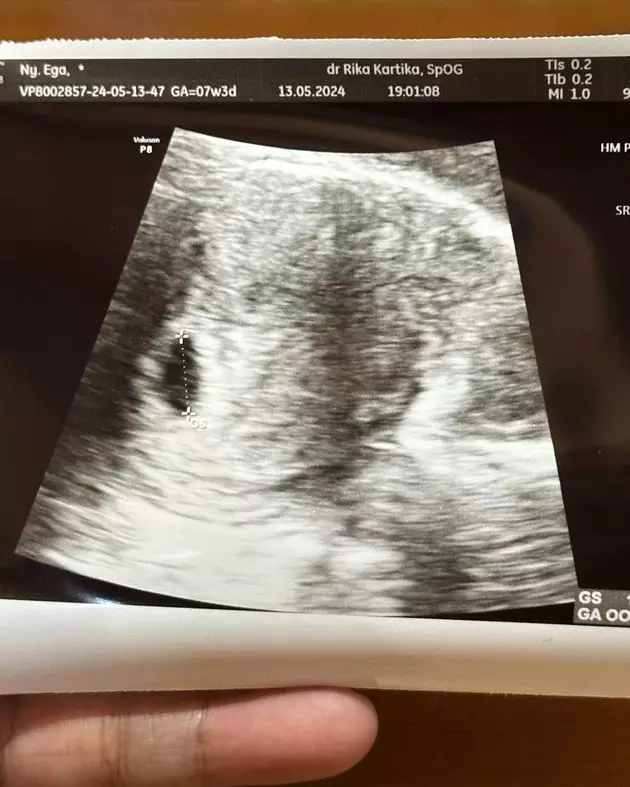

Pada slide terakhir postingan tersebut menunjukkan hasil USG Ega yang memperlihatkan janin kecil yang mulai tumbuh. Melihat dari foto USG-nya, usia kandungan Ega kini adalah 7 minggu. Itu artinya Ega akan bertemu sang buah hati di akhir tahun ini.